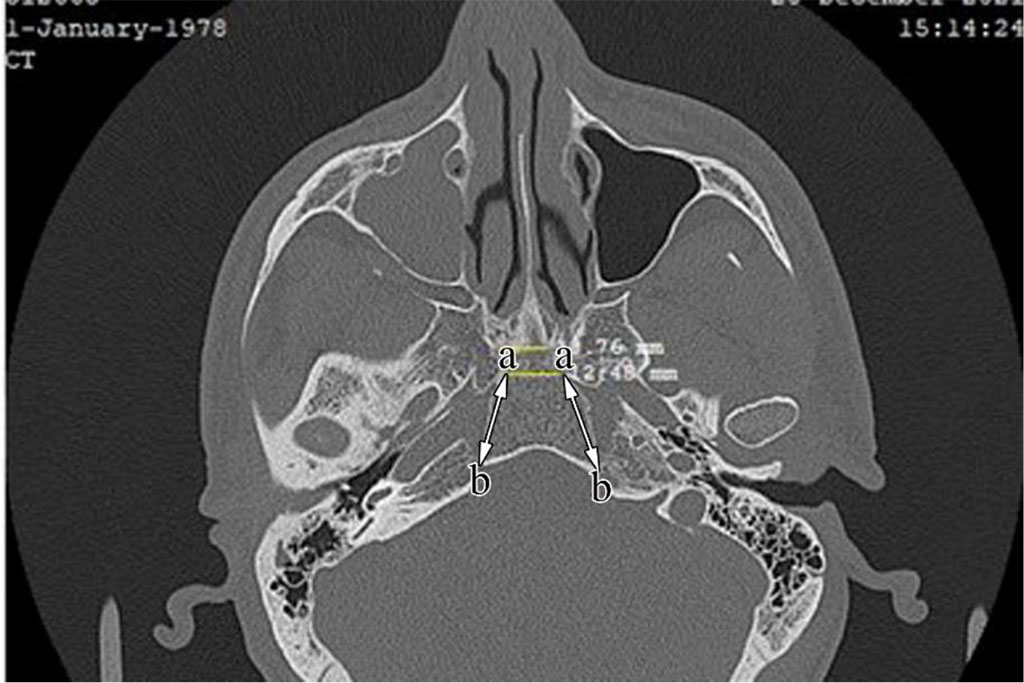

To measure the area of the hypophyseal fossa, we determined the distance between the middle (a) and posterior (b) clinoid processes, the length (h) and depth (l) between these lines (Fig. 1, Fig. 2). Taking into account that the hypophyseal fossa is trapezoidal in the vertical norm (norma verticalis), we calculated its area S= xh and its volume V xhxl using the formulas [8,9]. The obtained results were recorded and statistical analysis was carried out. Researches were carried out in 128-slice TOSHIBA tomograph. Measurements were made in axial and sagittal projections using RadiAnt DICOM Viewer program adapted for computer use. When analyzing indicators by variation groups, the mean score (M), standard error (±m), 95% confidence interval (95% CI), average structure - Me (median), quartiles (Q1, Q3), minimal and maximal (min, max) indicators were calculated. The difference between groups was assessed by ANNOVA (t-test). When comparing two or more groups, the results were performed with the non-parametric H-Kruskal-Wallis test. "0" hypothesis was rejected with statistical significance p < 0.050 (10).

Fig. 1. The distance between the middle (a) and posterior (b) clinoid processes in axial projection, in a 45-year-old man.